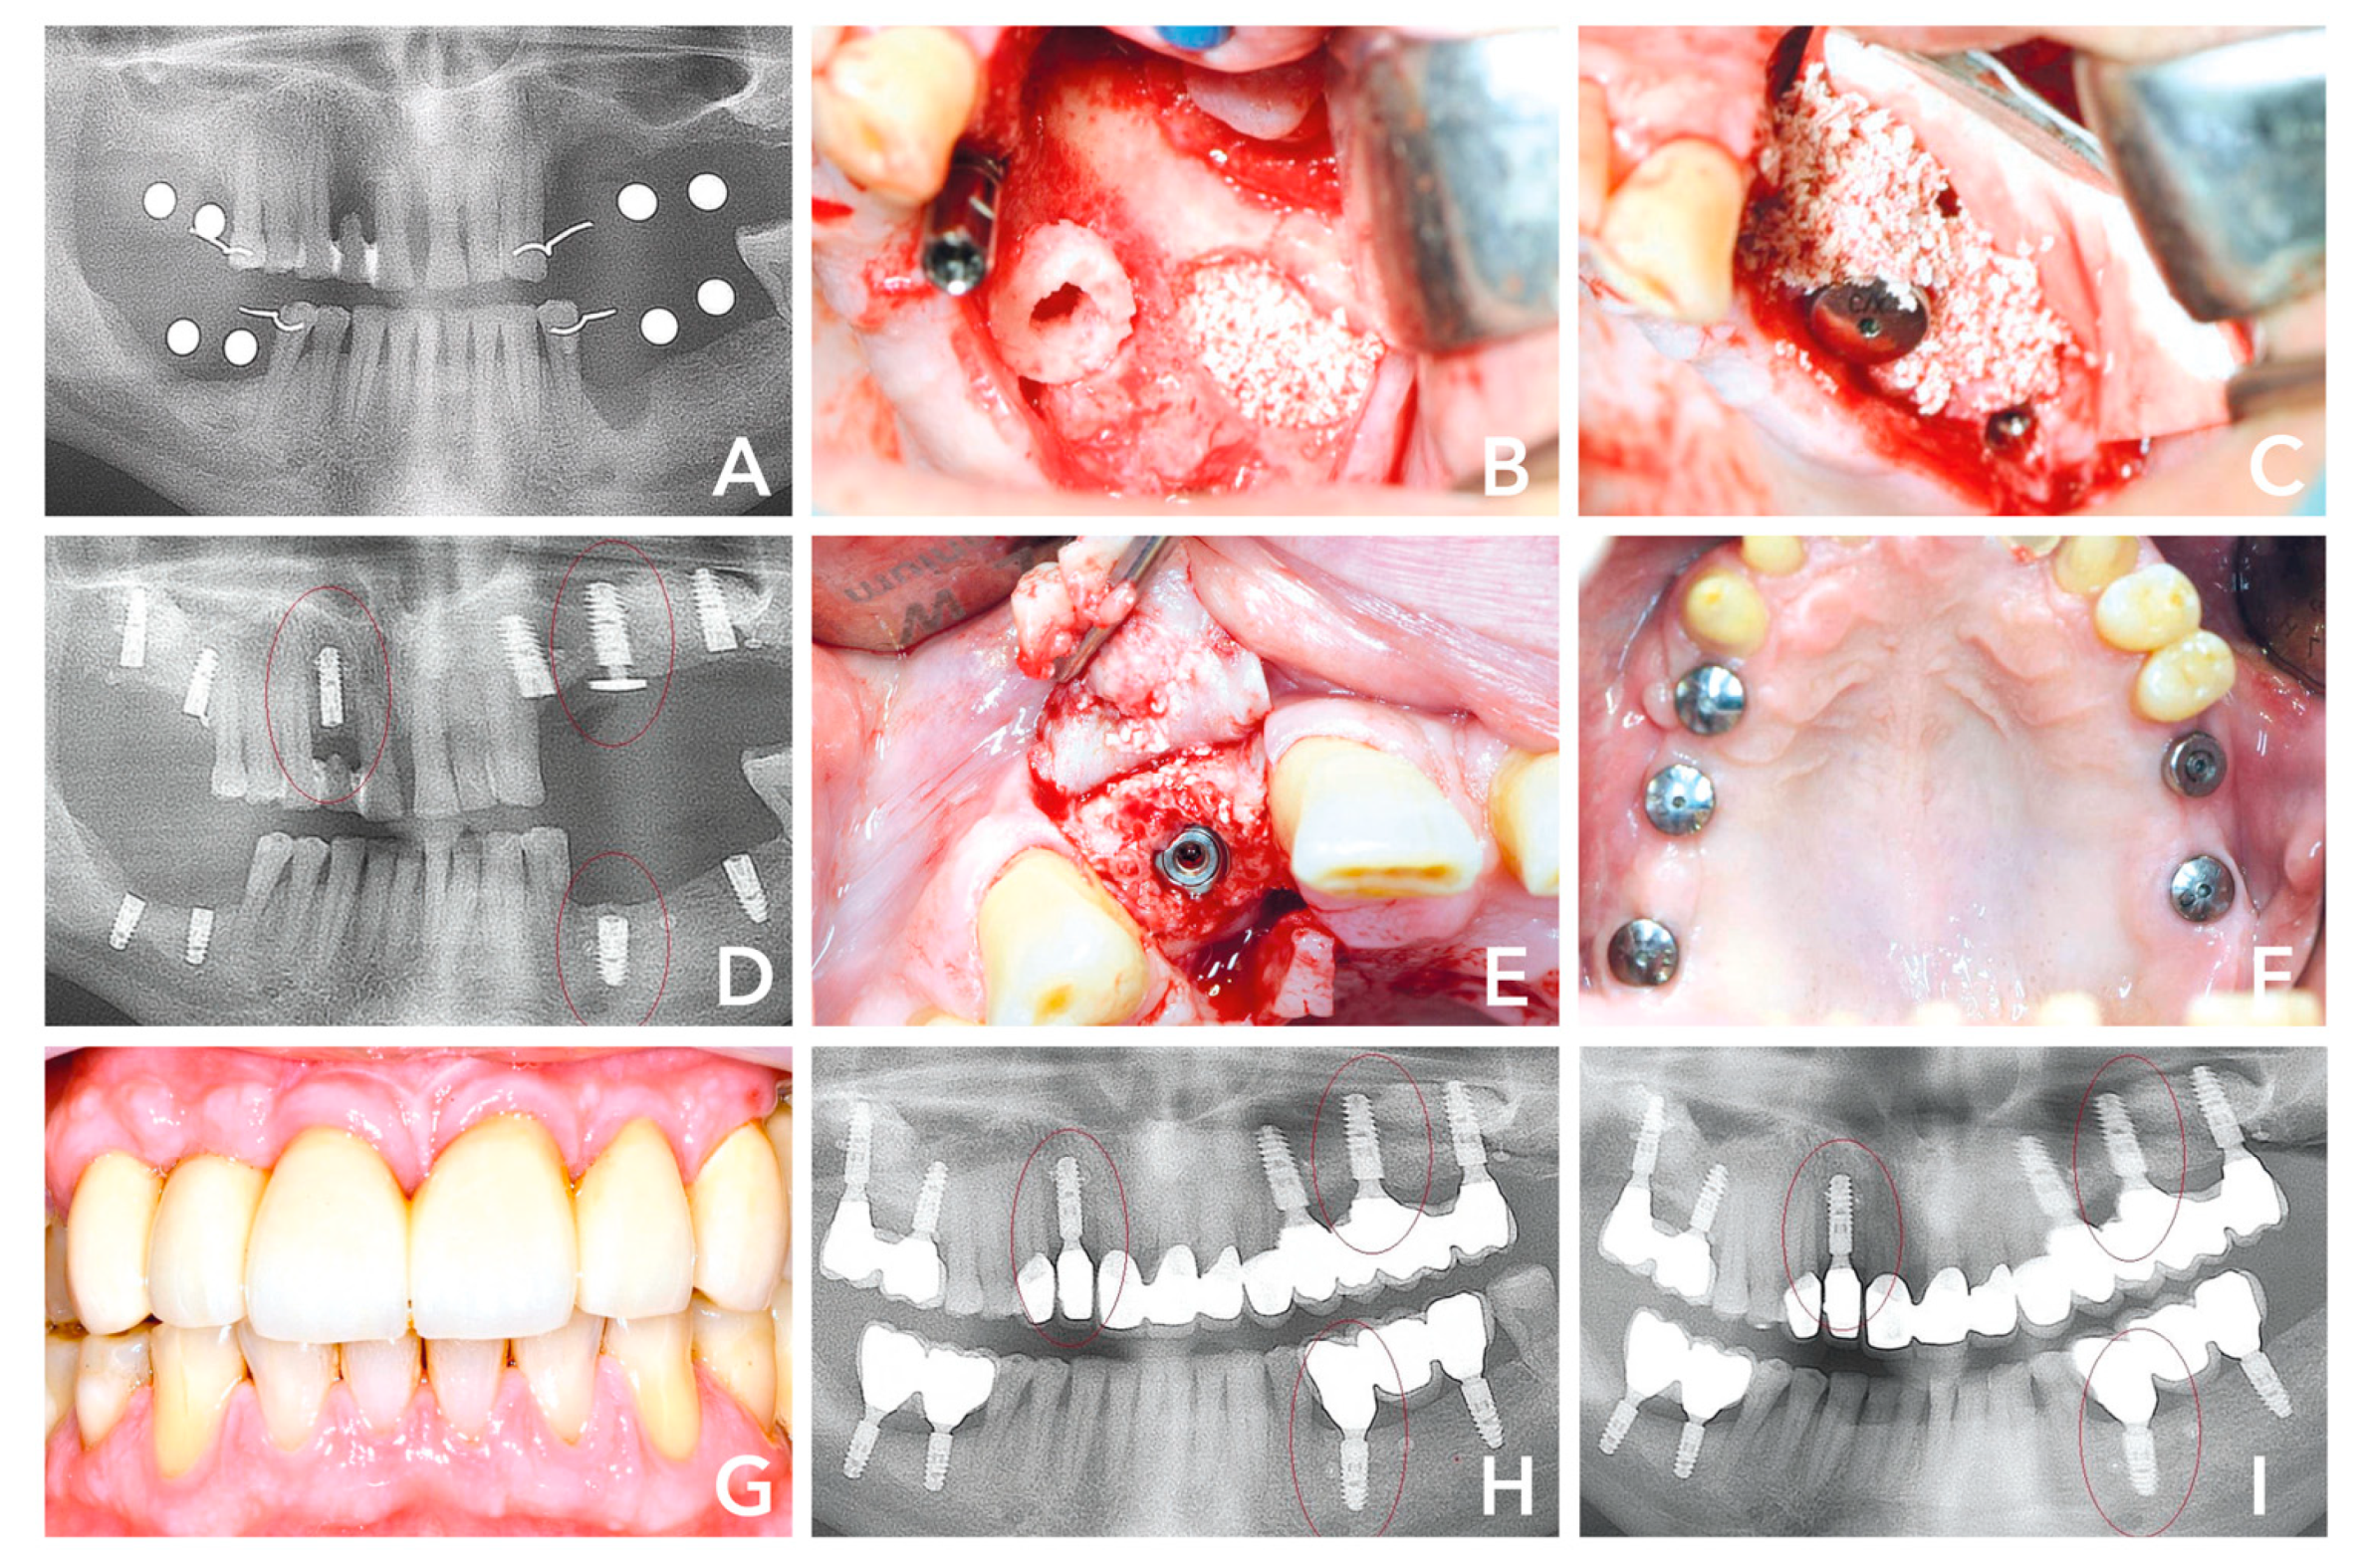

3.3. Case 3

The third case presented is a sinus floor elevation with a maxillary bone height of 0.4 -1.0 mm and the presence of sinus septa, which made that case even more challenging. The female 53-year-old patient without risk factors presented with a bridge retained posterior maxilla #24–28. Due to lack of physical load on #25–27, the site was missing sufficient bone to place implants. Additionally, the teeth #23–24 had to be extracted, as they lost attachment and were mobile (Figure 4A). The patient now desired a fixed prosthetic restoration with dental implants as soon as possible. As the bone height was only 1.5 mm at #27, the conventional treatment concepts would have meant placing the dental implant in a second stage after maturation of the bone grafting material in the sinus cavity. The Bone Ring Technique allows placing the implant simultaneously, as a fixation screw, and fixates the implant crestally within the bone graft in the sinus cavity. After being properly informed, the patient decided for a single stage approach with a cylindrical bone graft for her bone augmentation procedure at #27 and implant placement including external sinus floor elevation with a bone substitute. First, tooth #23 and #24 were extracted and a dental implant (Straumann® BLT Implant, Basel, Switzerland) was placed simultaneously at #23. The sinus septa at #25 and the bone loss in the sinus #26–27 were treated with external sinus floor elevation (Figure 4B). The lateral window was opened with a round bur and the Schneiderian membrane was gently lifted with a sinus membrane elevator. At #27, a cylindrical FDBA (maxgraft® bonering Ø 7-mm, botiss biomaterials, Zossen, Germany) was placed through the window and a bovine bone substitute (cerabone®, botiss biomaterials, Berlin) was filled into the sinus cavity (Figure 4C,D). A dental implant (Straumann® BLT Implant, Basel, Switzerland) was placed from the crest into the allogenic ring (Figure 4D). In order to secure the ring and prevent the dental implant and bone ring from moving into the sinus cavity, it was fixed with a Closure and Fixation Cap (Straumann®, Basel, Switzerland) (Figure 4E) that has a wider diameter than the implant to secure it crestally. In the end, the site #25 with the septum had sufficient bone to place a dental implant (Straumann® BLT Implant, Basel, Switzerland) with primary stability. The remaining free space in the sinus cavity was filled with bovine bone substitute (cerabone®, botiss biomaterials, Zossen, Germany) (Figure 4F). The lateral window was covered with a membrane and closed free of tension. The post-op radiological control showed well positioned implants (Figure 4G). Six months after surgery, the radiological check-up indicated stable bone in the sinus; hence the implants were uncovered, and the impressions were taken 1-week after (Figure 4H,I). The patient received the final prosthetic restoration only 6.5 months after initial surgery and was very satisfied with the final outcome (Figure 4J).

Figure 4. (A) Initial situation: Radiological image of bridge retained second quadrant with hopeless teeth #23 and #24. (B) External sinus floor elavation and implant placement #23. (C) Placement of a 7-mm bone ring block #27 and bovine bone substitute. (D) Implant placement. (E) Crestal placement of a fication screw to secure the bone graft and implant. (F) Implant placement in #25 and sinus cavity filled with bovine bone substitute. (G) Post-op x-ray. (H) Radiographical control 6 months after surgery. (I) Radiographical control 1 week later when the implants were uncovered and prosthodontic impression made. (J) Radiographical image of final prosthetic restoration 6.5 months after initial surgery.